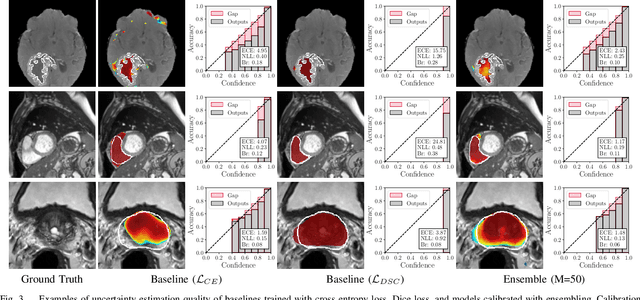

Abstract:Fully convolutional neural networks (FCNs), and in particular U-Nets, have achieved state-of-the-art results in semantic segmentation for numerous medical imaging applications. Moreover, batch normalization and Dice loss have been used successfully to stabilize and accelerate training. However, these networks are poorly calibrated i.e. they tend to produce overconfident predictions both in correct and erroneous classifications, making them unreliable and hard to interpret. In this paper, we study predictive uncertainty estimation in FCNs for medical image segmentation. We make the following contributions: 1) We systematically compare cross entropy loss with Dice loss in terms of segmentation quality and uncertainty estimation of FCNs; 2) We propose model ensembling for confidence calibration of the FCNs trained with batch normalization and Dice loss; 3) We assess the ability of calibrated FCNs to predict segmentation quality of structures and detect out-of-distribution test examples. We conduct extensive experiments across three medical image segmentation applications of the brain, the heart, and the prostate to evaluate our contributions. The results of this study offer considerable insight into the predictive uncertainty estimation and out-of-distribution detection in medical image segmentation and provide practical recipes for confidence calibration. Moreover, we consistently demonstrate that model ensembling improves confidence calibration.